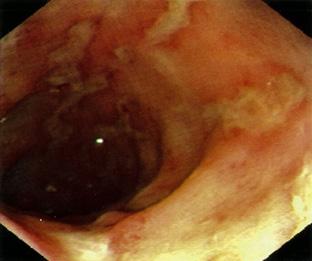

úlceras y erosiones lineales y redondas (algunas de color rojo más oscuro, algunas cubiertas por un exudado fibrinoso gris).

Figura 6. Esofagitis erosiva. Son visibles múltiples Figura 7. Esófago de Barret es una lesión premalgina. Metaplasia → displasia → adenocarcinoma (tercio inferior del esófago)